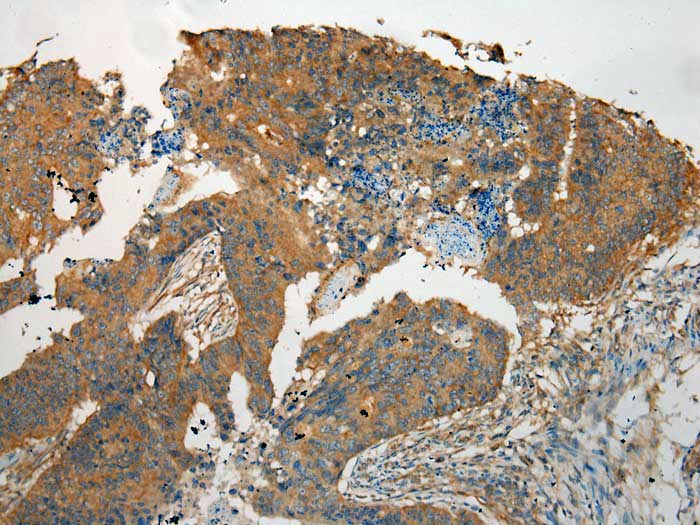

Immunohistochemical analysis of paraffin-embedded Human Colorectal cancer tissue using #40160 at dilution 1/100.

,

Immunohistochemical analysis of paraffin-embedded Human Tonsil cancer tissue using #40160 at dilution 1/100.